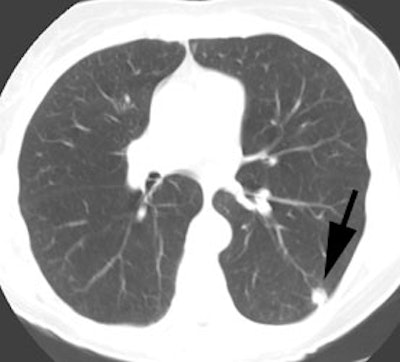

|

Unsuspected bone metastases: The patient shown below had a cavitary left lung non-small cell lung cancer. There was no uptake of tracer within the aortopulmonary window lymph nodes detected on CT to suggest metastases, however, unsuspected bone metastases were found in the left anterior 4th rib (black arrow) and lumbar spine (red arrows- not included in staging lung CT scan). The presence of bone metastases significantly alters patient prognosis and management. PET imaging provides a rapid whole body survey for the detection of unsuspected metastatic disease. |